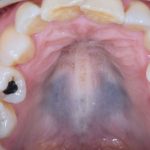

Fig. 8B Caso clinico di paziente con lesioni pigmentate relate all’assunzione di idrossiclorochina, presenti come macchie localizzate a vermiglio delle labbra e dorso lingua.

Home L’odontoiatria e le reazioni avverse a farmaci delle mucose orali Fig. 8B Caso clinico di paziente con lesioni pigmentate relate all’assunzione di idrossiclorochina, presenti come macchie localizzate a vermiglio delle labbra e dorso lingua.